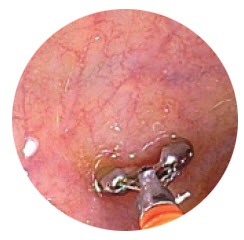

- Use blunt probe to push biopsy out of the base of the opened forceps cups

- Specimen can be squashed if pushed from top of open forceps

• Shaking biopsies off forceps into fixative can traumatize tissue and cause erosion of the epithelium

Reduce Crush Artifact

• Crush artifact is the tearing or compression of tissue often caused by the penetration of the forceps during biopsy

• Every biopsy has some crush artifact, typically at the periphery.

• Crushed tissue is difficult to interpret by a pathologist and can impact the ability to make definitive diagnoses

• Minimize the amount of tissue crushed by:

– Minimizing the handling of the specimen

– Not shaking the biopsy off the forceps

– Not pushing the biopsy out of the cup from the top